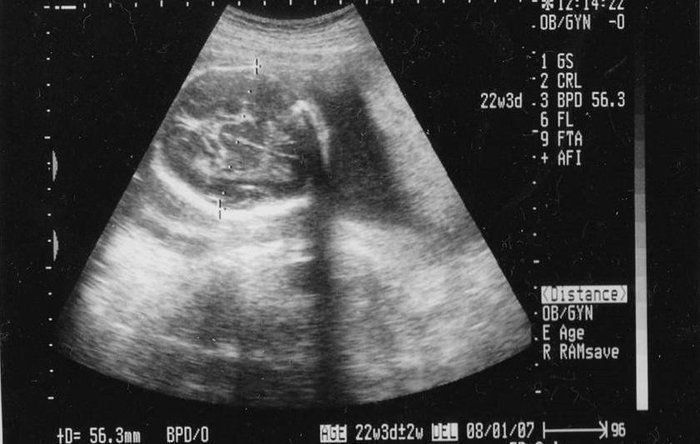

かえるさんの妊娠22週目のエコー写真

骨もくっきり分かります。「なんとなく女の子かも」と医師に告げられました。夫は男子希望だったため、そっけない反応。今から思い出しても腹立たしいです(笑)。おなかが出始めたので、ネット通販でマタニティーガードルや腹巻を買いそろえたのもこの時期。どこまで大きくなるか分からないのが不安でLLサイズにしましたが、正解でした。とにかく食欲がわいて、つわりで食べられなかった分をすぐに取り戻してしまいました。